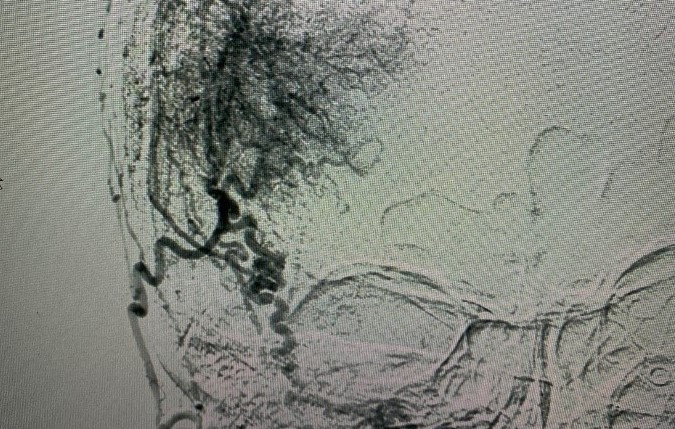

Kết quả chẩn đoán phát hiện người bệnh có u màng não lớn vùng thái dương bên phải, có nhiều mạch máu nuôi u. Bác sĩ lên kế hoạch phẫu thuật.

Trong quá trình chuẩn bị, bác sĩ phát hiện bà mắc bệnh lý mạch vành nên phải được hội chẩn thêm với chuyên khoa tim mạch. Vì khối u có quá nhiều mạch máu nuôi nên bác sĩ tiếp tục phải hội ý với chuyên khoa can thiệp nội mạch (DSA). Ê-kíp tiến hành làm tắc mạch nuôi u nhằm hạn chế máu chảy khi phẫu thuật.